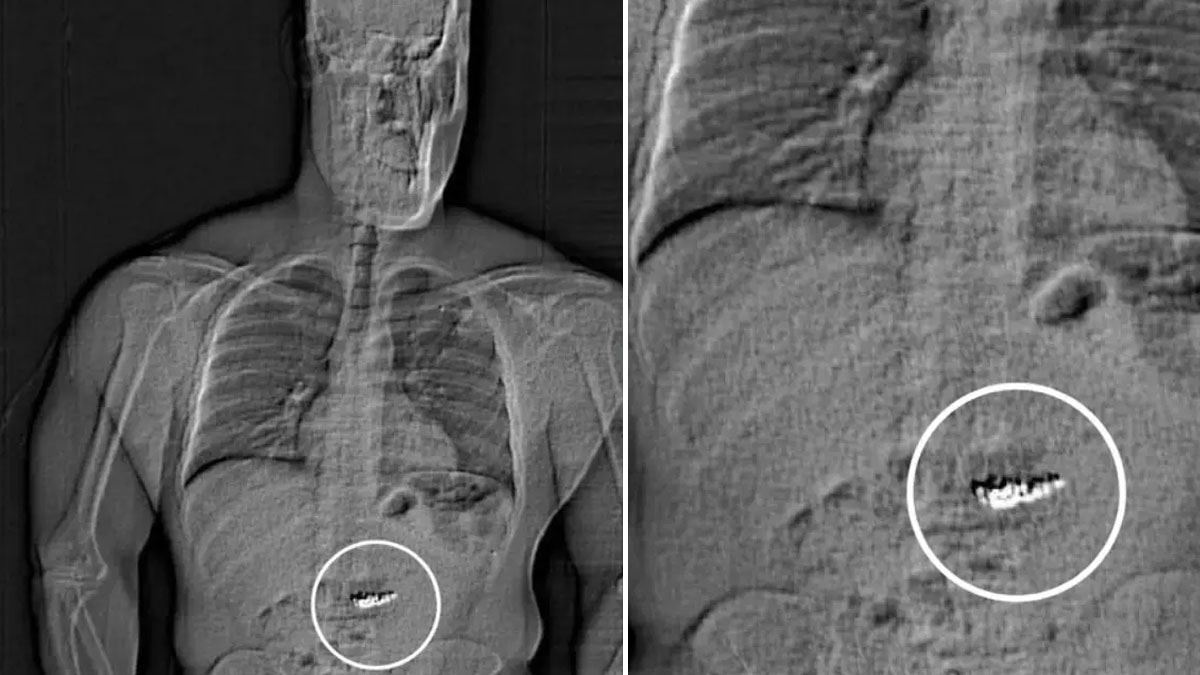

Hapishanede bulunan Gilder, bir anda yetkililere "Midemde olanlar için suçlanacak mıyım?" diyerek kendisini ele verdi. Gilder'e yapılan vücut taramasında sindirim sisteminde yabancı cisimler (küpeler) tespit edildi.

Raporda, "Bu yabancı cisimlerin, soygunda çalınan Tiffany&Co küpeleri olduğu düşünülüyor ancak Gilder'in sisteminden çıktıktan sonra toplanarak doğrulanması gerekecek" ifadeleri yer aldı.